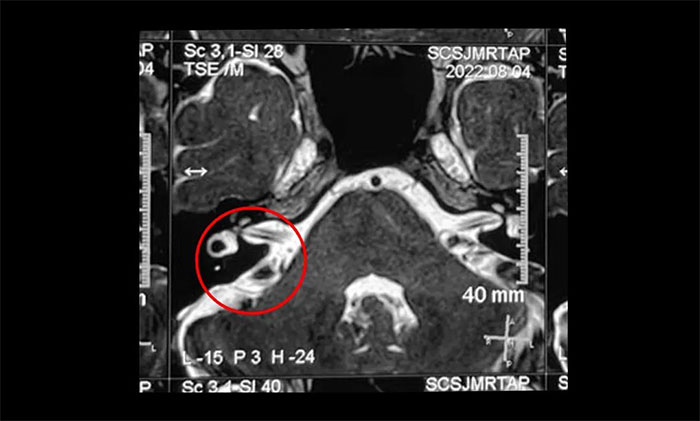

▲ 右側(cè)三叉神經(jīng)與周圍小血管關(guān)系密切

結(jié)合影像資料,楊忠旭教授指出患者右側(cè)三叉神經(jīng)與周圍小血管關(guān)系密切,手術(shù)指征明顯,未見(jiàn)明顯手術(shù)禁忌癥。